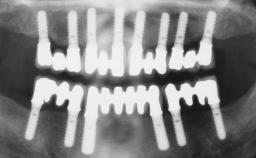

Conventional Loading of Eight Implants in the Maxilla and Final Restoration with a Full-Arch Gold-Ceramic FDP

# of Implants 8

Type of Implants One-Piece

Defining Characteristics Fully edentulous upper jaw to be rehabilitated with four or more implants

Modality Fixed hybrid bridge on 5+ implants